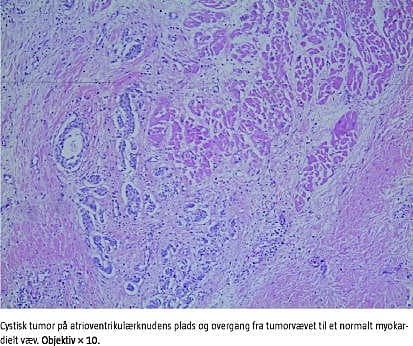

På grund af den uventede død blev der foretaget retslægeligt ligsyn med efterfølgende retslægelig obduktion. Ved obduktionen blev de kliniske fund bekræftet. Derudover var de postmortelle virologiske og bakteriologiske undersøgelser negative. Der blev påvist lungebetændelse. Grundet pigens alder ansås medfødt AV-blok ikke som muligt, og moderen blev derfor ikke undersøgt for Sjögrens syndrom antistof A og Sjögrens syndrom antistof B. Pigens myokardie var uden specifikke histopatologiske forandringer, men ved undersøgelse af hjertets ledningssystem blev påvist en tumor på AV-knudens plads. Histopatologisk var denne tumor tubulær til acinær i struktur, beklædt med et kubisk epitel, stedvist med overgangslignende epitel og omgivet af et fibrøst stroma. Der var hverken cellulær pleomorfi eller mitoser. I randzonerne var et kronisk betændelsesinfiltrat. Immunhistokemiske undersøgelser tydede på celler af endodermal oprindelse.